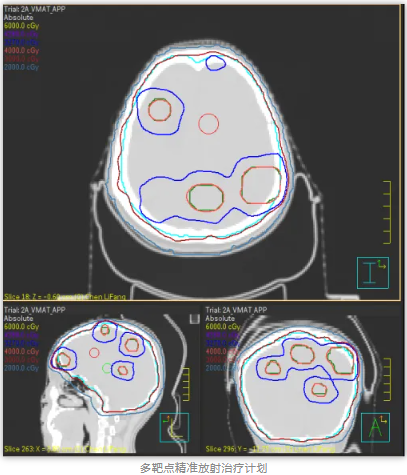

MTPRT是一种先进的放疗方法,旨在使用CT、MRI和PET等影像技术精确识别和定位多个肿瘤靶点。针对不同肿瘤靶点的生物学特性,制定优化的放射剂量分布,同时照射多个肿瘤靶点。在治疗过程中,通过实时影像监控患者和肿瘤位置变化,动态调整治疗方案。该技术综合利用影像引导放疗(IGRT)、立体定向放射治疗(SBRT)和调强放射治疗(IMRT)等手段,通过高精度影像技术和先进的计算算法,实现对复杂肿瘤的有效治疗,同时最大限度地保护周围健康组织。该技术代表了放射治疗领域的前沿发展,具有广泛的临床应用前景和重要的研究价值。

王女士最近很苦“脑”,发现肺部肿瘤复发转移到了脑部,新发病灶多达6颗。为提高放疗疗效、减少放射损伤,肿瘤科团队提出采用新近开展的 “多靶点精准放射治疗技术(MTPRT)”进行治疗。相较于全脑放疗而言,该技术不容易脱靶,能够更有效保护靶区外的正常脑组织,降低患者的副反应。

在肿瘤中心专家团队指导下,放疗医生、物理师、治疗师、护士等各专业人员紧密配合,王女士经历了“患者定位—大孔径CT下模拟定位—多靶点肿瘤计划设计—治疗前的计划验证和位置验证—适时治疗”的放疗流程,目前已经顺利完成了一个疗程的放射治疗,其间无明显不适,脑部的转移瘤也基本消失。